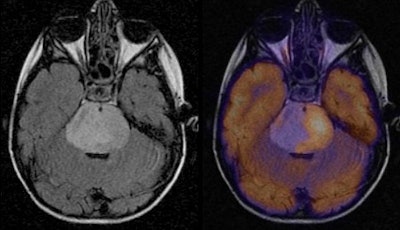

MRI scans were performed within two weeks of PET imaging and prior to therapy in all cases. PET results were then coregistered with MR images.

"PET is really quite good in terms of giving us functional and physiological information about the tumor, and the standard MRI for coregistering gives us the structural and anatomic configuration of the tumor," added study co-author Dr. Tina Young Poussaint, director of the Neuroimaging Center. "So we looked with MRI within the confines of the tumor and we looked to see where the metabolic activity was within each tumor type."

Perhaps unsurprisingly, the researchers found that FDG uptake and MRI enhancement varied by tumor type. On average, glioblastoma multiforme and medulloblastoma had uniform, intense FDG uptake throughout the tumor. Meanwhile, brainstem glioma had low levels of FDG uptake in less than 50% of the tumor. Ependymoma also had low-level FDG uptake throughout the tumor.